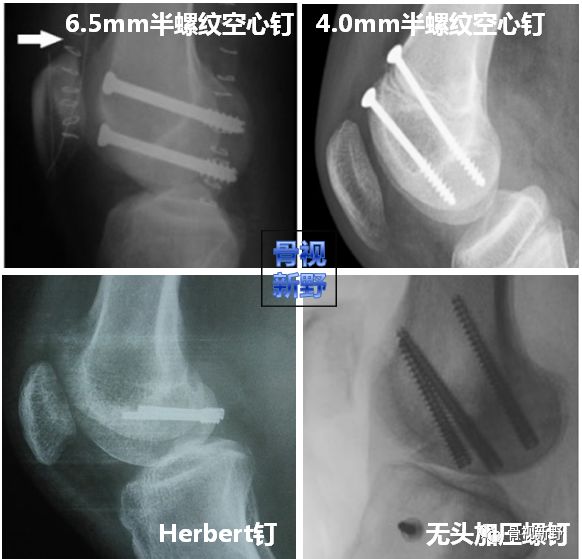

螺钉种类   可用于Hoffa骨折内固定的螺钉种类包括松质骨螺钉、 Herbert钉、 无头加压螺钉等;直径6.5mm的半螺纹空心钉、直径4.5、4.0、3.5mm的皮质骨螺钉/半螺纹空心钉等。

无头加压螺钉:与普通螺钉采用埋头的方法置入相比,无头加压螺钉置入后在关节软骨面上留下的切迹较小,允许多枚置钉;无头加压螺钉可增加骨折块间压力,其抗轴向压缩及极限负荷明显大于空心拉力螺钉,可极大增加骨折端的稳定性。